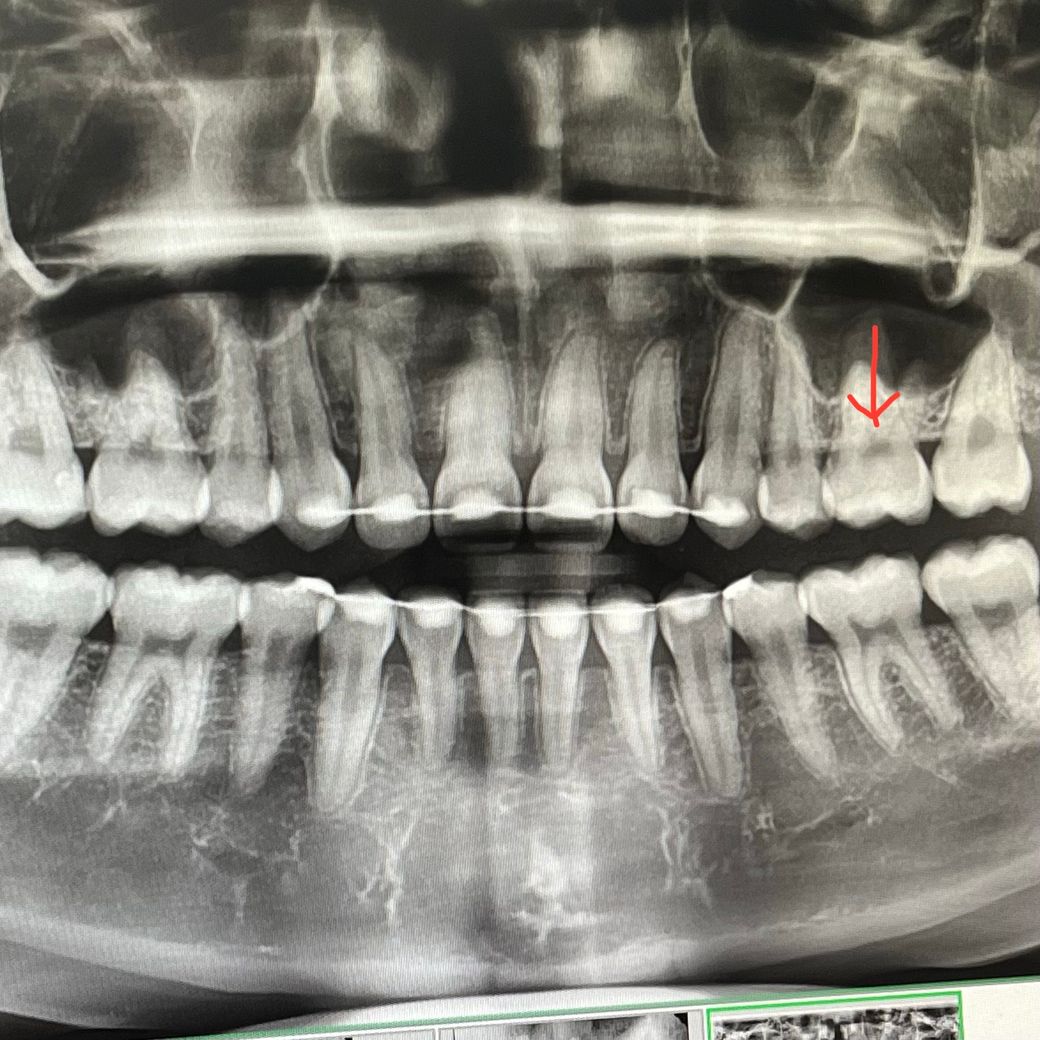

보다보니 표시한 치아에 인접면 충가 있는거 아닌가 싶은 생각이 들더라구용

치아 사이가 중첩되어 나타나 있기 때문에 해당 사진으로는 충치 감별이 힘듭니다.

파노라마 사진으로 인접면 사진은 정확히 보기 힘듭니다. 조그만한 사진을 찍어보시면 제대로 파악하실수 있습니다.

해당 보위는 치아가 겹쳐 있음으로써 보이는 음영을 수 있습니다.

정확한 확인을 위해서는 치근단사진을 찍어 보는 것이 더 좋습니다.

화살표가 가르키는 것은 충치가 아니고 치수입니다.

인접면 충치를 보다 정확하게 방사선 사진으로 확인하기 위해서는 교익방사선사진이 필요합니다.

파노라마 사진상으로는 실제로 오류가 있으며 특히 해당 치아의 해당 부위는 치아 뿌리 2개가 겹쳐있어서 충분히 왜곡될 수도 있습니다.

보통 인접면 충치와 cervical burn out 감별이 필요한데 해당 부위는 cervical burn out 위치에 좀 더 가깝습니다

또한 인접면 충치는 환자 본인의 증상과 육안으로 확인하는 것도 중요합니다